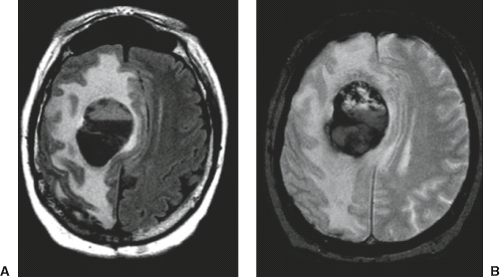

Adult Brain Tumors | Radiology Key

Adult Brain Tumors | Radiology Key from i0.wp.com

A brain tumor is a mass of abnormally growing cells in the brain or skull. Any growth inside such a restricted space can cause problems. Brain tumors are masses of abnormal cells within the brain.